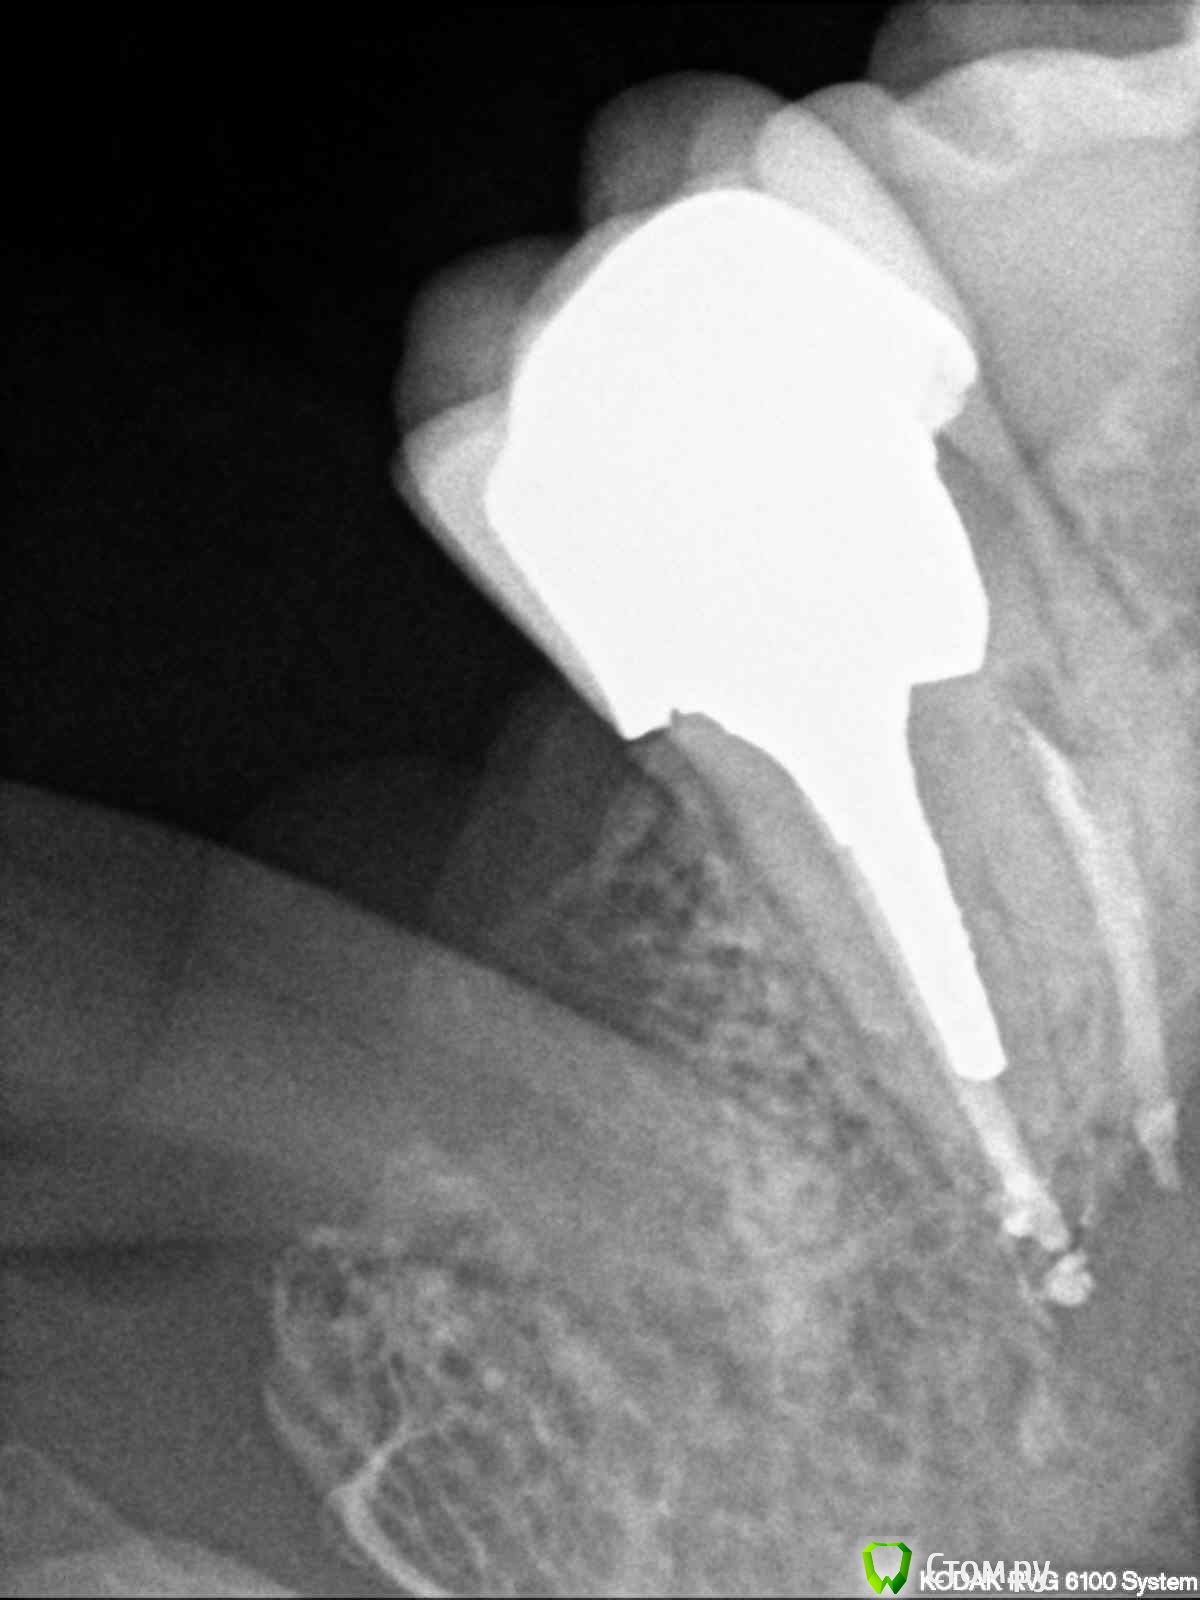

1) на 27 зубе периодонтит и эндодонтическое лечение неудачно.

Уважаемые врачи, я сделала прицельные снимки 27 и 43 зубов. Если несложно, оцените пломбировку каналов. Не знаю какие снимки боллее удачные, поэтому разместила по 2 снимка каждого зуба. На 43 зуб надо ставить пломбу или коронки? Мнения в разных клиниках разошлись. Заранее спасибо за ответ.

post-36178-0-32966600-1385561030_thumb.jpg

post-36178-0-95622200-1385561042_thumb.jpg

post-36178-0-56636700-1385561054_thumb.jpg

post-36178-0-84859900-1385561065_thumb.jpg